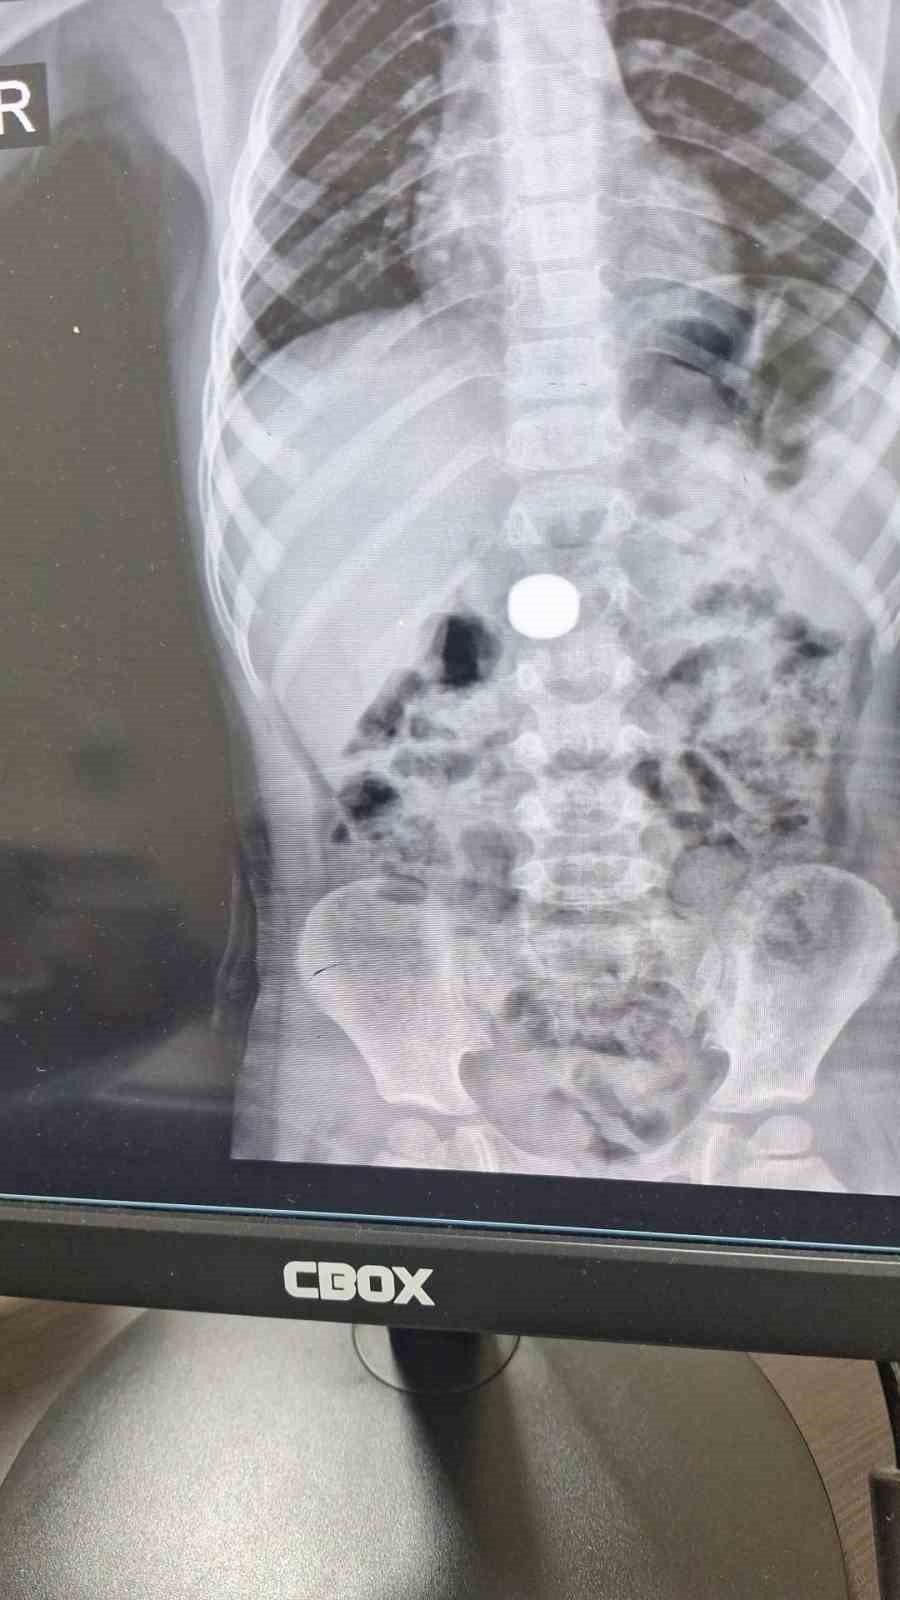

Karaman’da iki mıknatıs yuttuğu belirlenen 4 yaşındaki İ.K., Karaman Eğitim ve Araştırma Hastanesi Acil Servisi’ne kaldırıldı. Ailesinin şüphesi üzerine yapılan tetkiklerde, çocuğun ince bağırsağında iki adet mıknatıs bulunduğu tespit edildi.

Çocuk Cerrahisi Uzmanı Doç. Dr. Mehmet Uysal, gözetim süresince çekilen filmlerde mıknatısların yer değiştirmediğini belirtti.

Uysal, “Hastayı genel anestezi altında ameliyata aldık. İnce bağırsakta iki mıknatısın birbirine yapışık halde olduğunu gördük. Gerçekleştirdiğimiz operasyonla mıknatısları çıkardık. Ameliyat sonrası hastamız üçüncü gününde taburcu edildi. Şu an genel durumu iyi” ifadelerini kullandı.